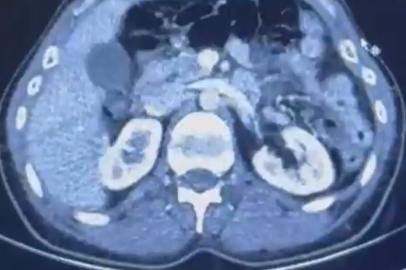

Edinilen bilgiye göre Narkotik Suçlarla Mücadele Şube Müdürlüğü ekiplerince uluslararası uyuşturucu madde ticareti yapan kurye şahıslara yönelik gerçekleştirilen çalışmalarda, İran’dan Türkiye'ye uyuşturucu madde getirdiği tespit edilen şüpheli şahısların yakalanması amacıyla operasyon düzenlendi. Düzenlenen operasyonda; S.C., R.B.C. ve G.M. yakalandı. S.C. ve R.B.C.'nin Kayseri Şehir Hastanesi'nde yapılan iç beden muayenelerinde, mide kısımlarında bulunduğu tespit edilen 50 adet kapsül şeklinde toplam 554 gram uyuşturucu madde ele geçirildi. Şüpheliler gözaltına alınarak haklarında 'Uyuşturucu Madde Ticareti Yapmak' işlem başlatıldı. Kayseri İl Emniyet Müdürlüğü'nden yapılan açıklamada; "Uyuşturucu ve uyarıcı madde satıcılarına karşı yürüttüğümüz mücadele aralıksız ve kararlı bir şekilde devam edecektir" denildi.